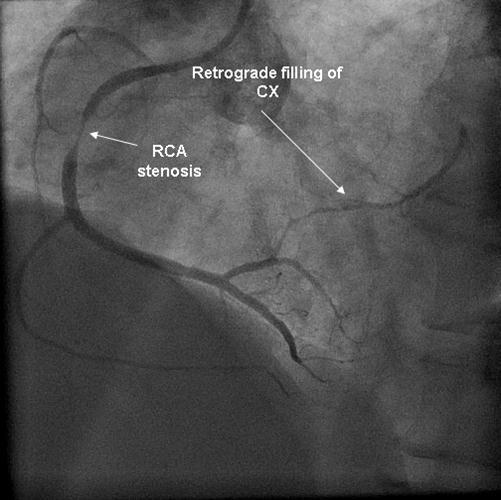

Coronary angiography was again performed. On injections into the left system, collaterals to the distal RCA were demonstrated (figure 1), arising from the left circumflex coronary artery (CX). Injections into the RCA demonstrated tight in-stent restenosis, (figure 2) and a drug eluting stent was successfully implanted. After the angioplasty, injections into the RCA were seen to retrogradely fill the CX (figure 3). The suspicion arose that maybe the left coronary artery had been inadvertently damaged during angiography, so the left coronary was again cannulated and injections performed, demonstrating entirely normal left main and CX arteries. However, the collateral flow that had previously been demonstrated from the CX to the RCA was no longer apparent. On review of the previous angiogram, it was noted that the RCA retrogradely filled the CX despite the original significant stenosis (figure 4). In essence, it became apparent that the bidirectional filling of the RCA from the CX and vice versa was in fact a direct continuity between the vessels and not collaterals, as free flow was noted from the RCA to the CX even when both arteries were completely patent.

Figure 4.Injection into the RCA in the first angiogram, with retrograde filling of CX.

There are a few interesting points about our patient's case. He demonstrated dynamic changes in the direction of coronary flow, in parallel to the development of a stenotic lesion. Firstly, in the original angiogram, there was flow from the RCA to the CX even though there was a significant stenosis. In his second angiogram, however, no such flow was demonstrated, maybe due to the longer and more critical restenosis that had developed in the stent. Secondly, at the start of both angiograms, there was flow from the CX to RCA, an appropriate finding as a collateral vessel in the presence of an obstructive lesion in the RCA. Thirdly, it seems that when both arteries are fully patent, the bidirectional flow changes to unidirectional, from the RCA to the CX.